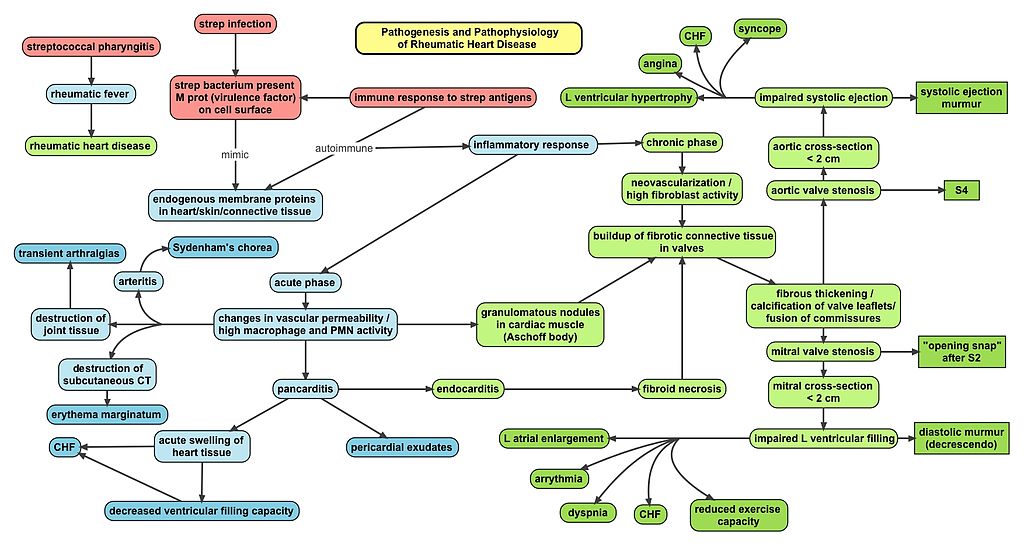

Acute rheumatic fever is caused by group A beta-hemolytic streptococci.

Children are susceptible to this systemic consequence of streptococcal pharyngitis, often known as strep throat, 2 – 3 weeks after an episode.

Acute rheumatic fever is caused by molecular mimicry due to a bacterial M protein that resembles proteins in human tissue.

The mitral valve is the most affected cardiac valve.

Small vegetations accrue on the valve along the lines of closure that result in mitral regurgitation.

Histology classically shows reactive histiocytes with slender, wavy nuclei are known as Anitschkow cells, Aschoff bodies, gigantic cells, and fibrinoid material.

The most frequent cause of death in acute rheumatic fever is myocarditis.

Erythema marginatum is a non-pruritic annular rash with erythematous borders that often affects the trunk and limbs.

Pericarditis causes friction rub and chest pain.

Sydenham chorea is the rapid, involuntary muscle movements.

The acute attack normally goes away, but it could turn into a persistent case of rheumatic heart disease.

Relapse of the acute phase and increased risk for chronic disease are brought on by repeated exposure to group A hemolytic streptococci.

Chronic Rheumatic Heart Disease

Chronic rheumatic heart disease develops when rheumatic fever-related valve scarring leads to stenosis with the classic fish-mouth appearance.

In chronic rheumatic heart disease, the chordae tendineae and cusps thicken as a result of the mitral valve being involved almost always.

Quite often the aortic valve is involved, which results in the commissures fusing together.

Other valves are less commonly involved and complications include infectious endocarditis.